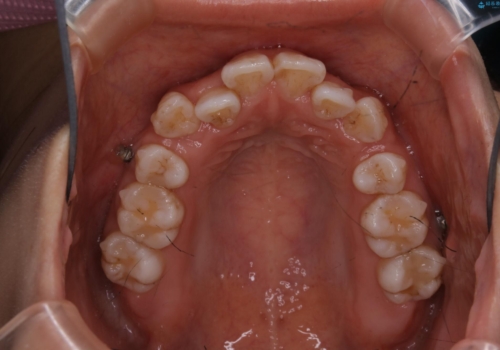

インビザライン単独での抜歯矯正治療

- インビザラインFULL

1日20時間以上、正しくインビザラインを使用して頂いたおかげで、ワイヤーに切り替えることなく矯正治療を終了することが出来ました。抜歯症例でしたが比較的短期間で見た目が劇的に改善し、大変喜んでいただけました。